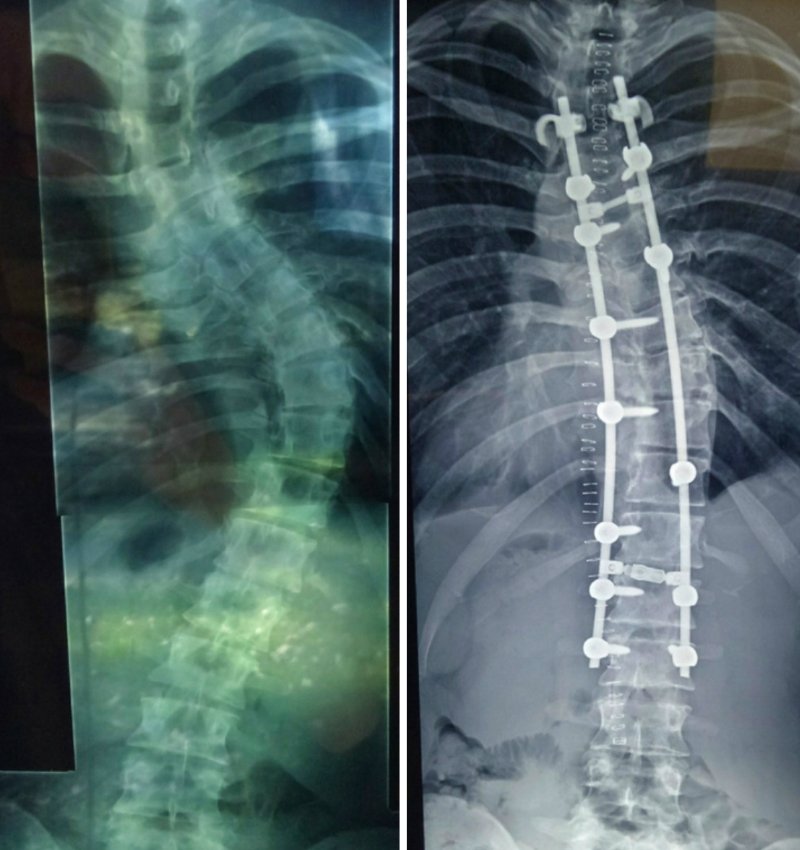

Фото первого подтягивания на перекладине, сделанное после коррекции позвоночника. Впереди еще много работы, но самое трудное уже позади.